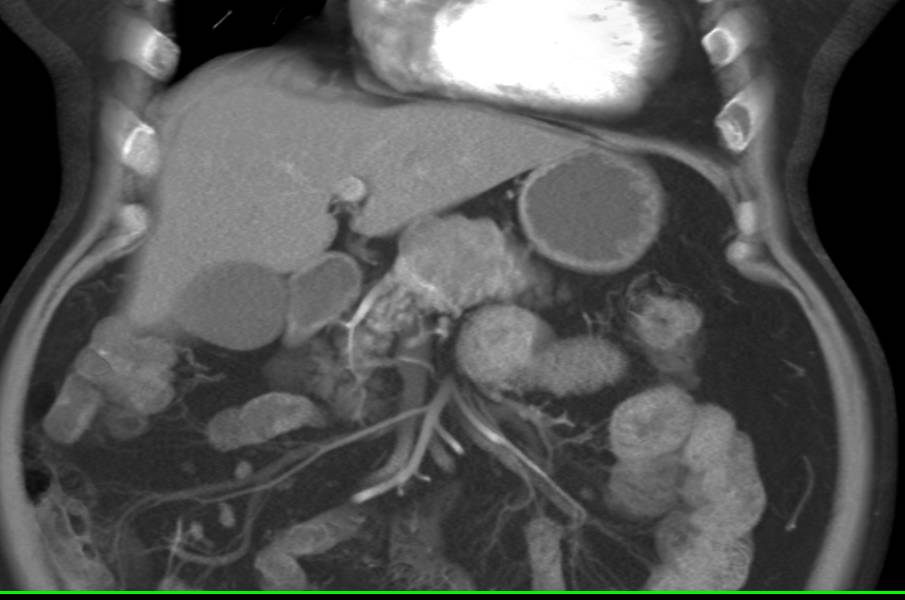

Vascular Metastases to the Tail of the Pancreas in Patient with History of Renal Cell Carcinoma